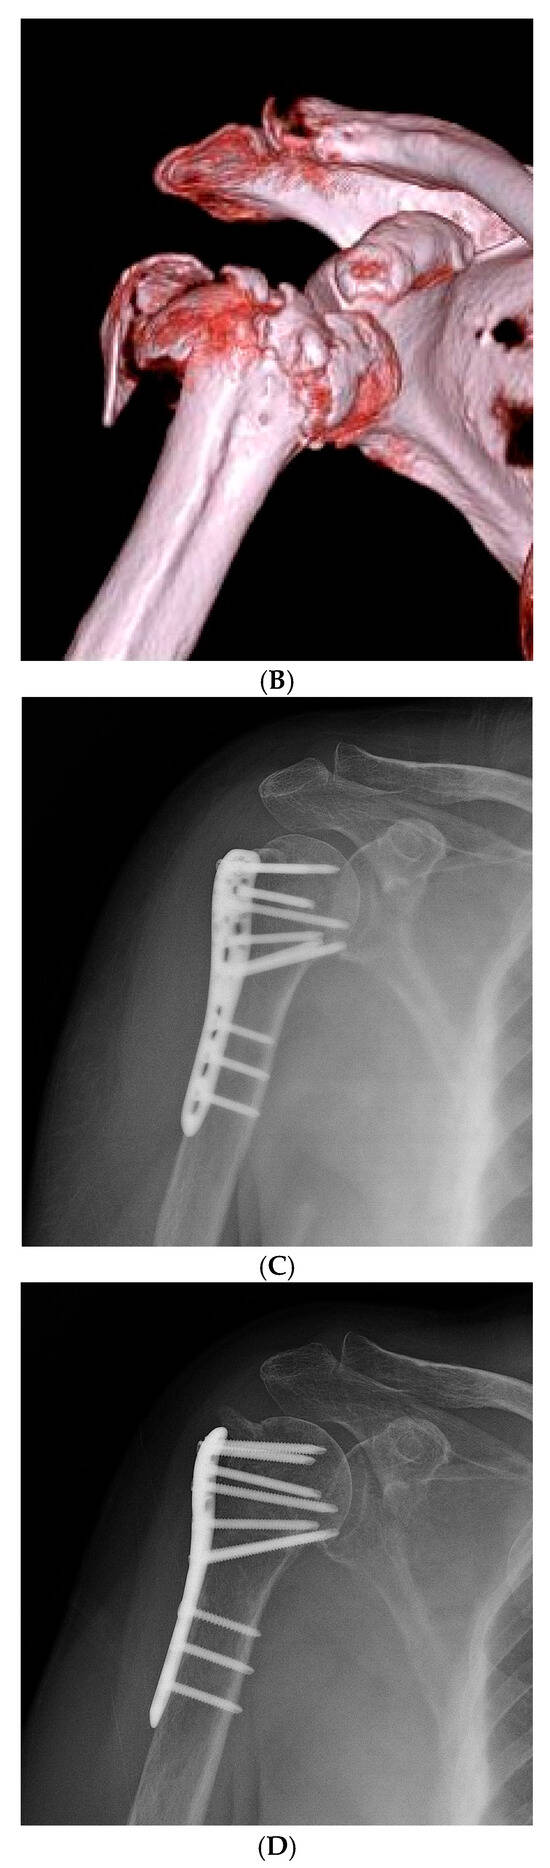

Figure 3.

Representative Case 2: 58-year-old male with Neer type-4 valgus impacted proximal humeral fracture treated with ORIF and conventional rehabilitation. (A) Preoperative AP radiograph showing severely displaced valgus impacted fracture. (B) Preoperative axial CT scan illustrating fragment displacement and rotation. (C) Immediate postoperative AP radiograph showing satisfactory reduction and internal fixation. (D) 24-month follow-up AP radiograph demonstrating complete fracture healing, and maintained functional range of motion.